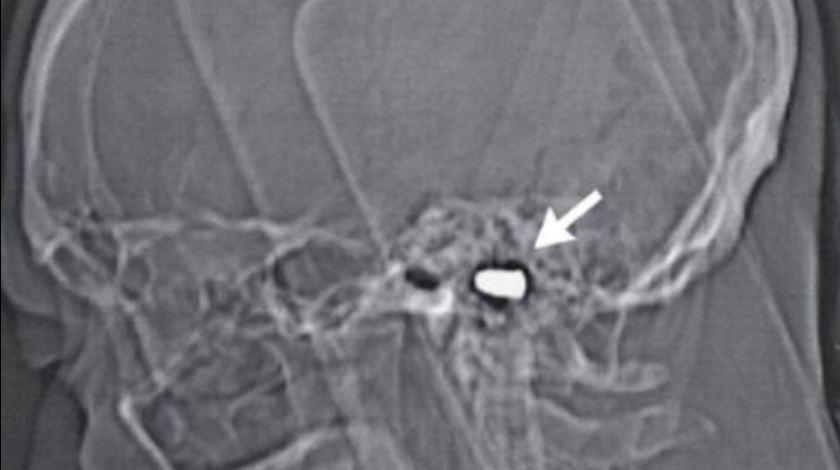

Η σφαίρα που δέχτηκε από τον αδερφό του πέρασε από τη μύτη του και στη συνέχεια κατέληξε στον εγκέφαλο του. Οι γιατροί τότε δεν την αφαίρεσαν από φόβο μήπως προκαλέσουν μεγαλύτερη ζημιά. Το θέμα όμως επανήλθε στο προσκήνιο πρόσφατα όταν ο άντρας υπεβλήθη σε επέμβαση καρδιάς.

Οι γιατροί σε καρδιολογικό κέντρο της Ρωσίας εντόπισαν τη σφαίρα κάνοντας ακτινογραφία και διαπίστωσαν ότι δεν είχε του προκαλέσει όλα αυτά τα χρόνια το παραμικρό νευρολογικό πρόβλημα. Μάλιστα αποφάσισαν να αφήσουν τη σφαίρα εκεί που είναι καθώς απέκλεισαν το ενδεχόμενο να αποβεί επικίνδυνη έπειτα από τόσα χρόνια.